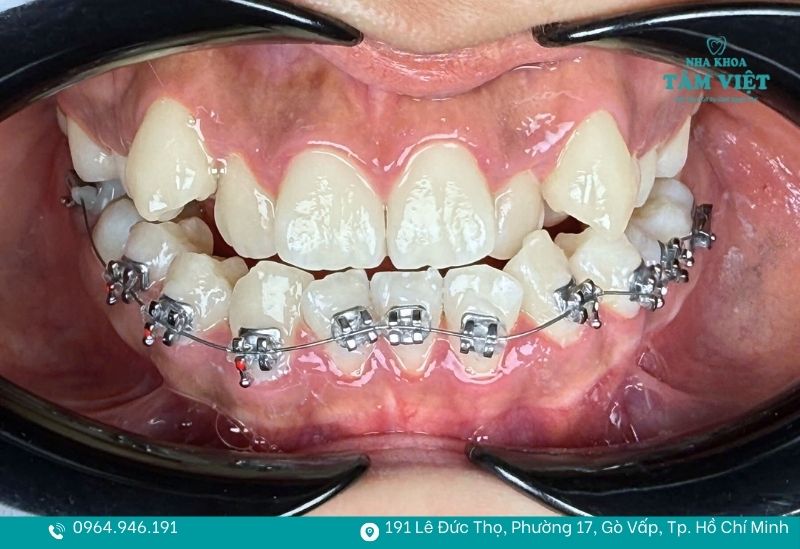

Để trả lời rõ ràng cho thắc mắc “trồng răng có niềng được không”, các bác sĩ tại Nha khoa Tâm Việt sẽ phân loại dựa trên phương pháp phục hình bạn đã thực hiện. Việc niềng răng khi đã trồng răng giả hoàn toàn khả thi, nhưng sẽ có những giới hạn nhất định.

Trường hợp CÓ thể niềng sau khi trồng răng

| Trồng 1–2 implant ở răng hàm phía trong | implant cố định độc lập, không ảnh hưởng toàn bộ cung răng | Dịch chuyển các răng tự nhiên xung quanh

implant đóng vai trò neo cố định |

| implant đặt đúng vị trí theo kế hoạch | Trụ đã ổn định, khớp cắn chuẩn | Niềng bằng mắc cài hoặc Invisalign

Chỉ tác động lên răng thật còn lại |

Dù câu trả lời cho việc trồng răng có niềng được không là có thể, nhưng đây vẫn là một kỹ thuật nha khoa phức tạp. Để đạt được kết quả như ý mà vẫn bảo vệ được các trụ implant hay răng sứ đắt tiền, bạn nên lưu ý:

Quy trình xử lý cho những trường hợp đặc biệt này bắt đầu bằng việc thăm khám và tầm soát sức khỏe răng miệng toàn diện. Thay vì chỉ tập trung vào việc dàn đều răng, bác sĩ sẽ đánh giá kỹ lưỡng trồng răng có niềng được không qua độ tích hợp của trụ implant và sức khỏe của các cùi răng thật bên trong mão sứ. Mọi vấn đề về viêm nướu hay mật độ xương đều được xử lý dứt điểm.